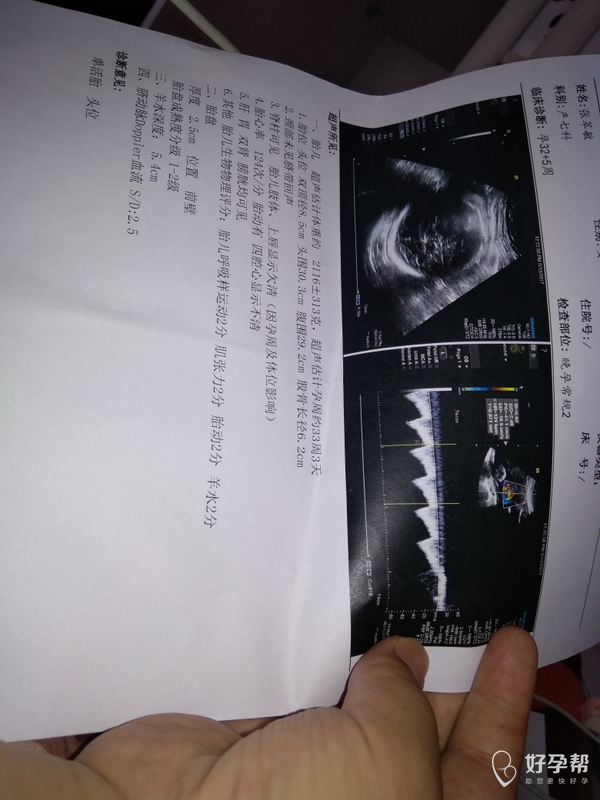

刚刚检查结果,求解答医生

你好,空腹血糖增高,需要做葡萄糖耐量试验,血常规提示有轻度的贫血,需要来纠正贫血。

还有血糖测的7.1,医生建议做糖耐,血糖偏高,还有必要做糖耐吗,求解答